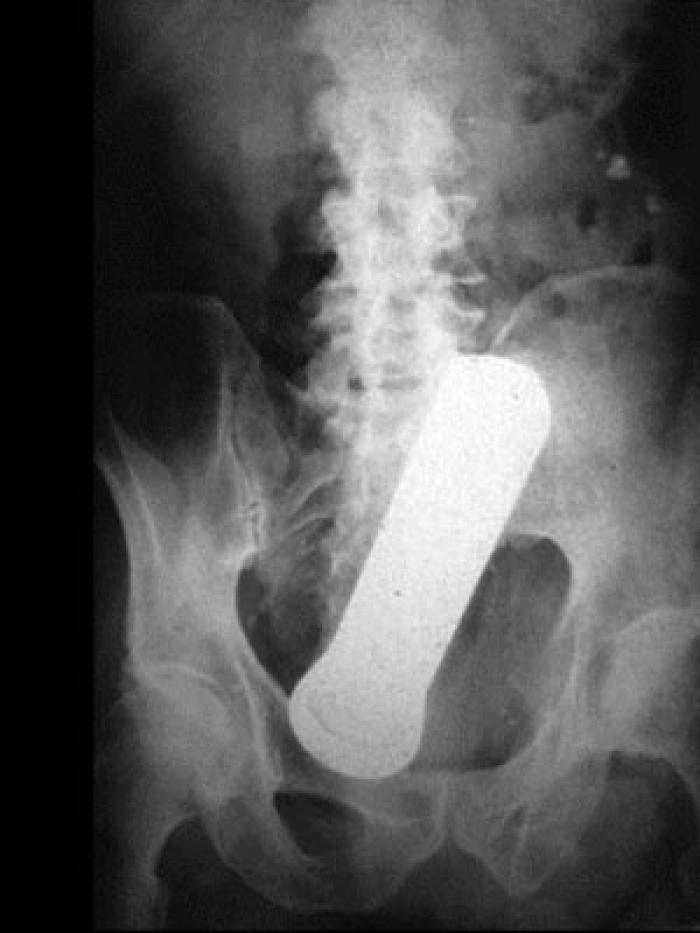

Polițiștii au parte de cele mai amuzante întâmplări, iar infractorii tind să aibă cele mai inventive modalități de a ascunde obiecte, alegând de multe ori posteriorul